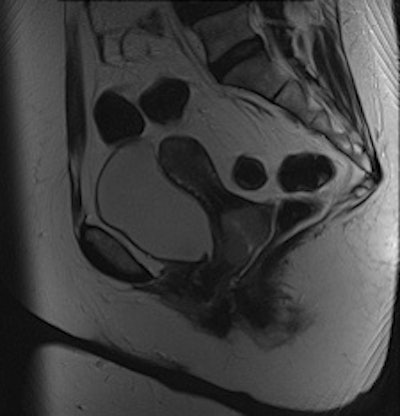

Adenomyosis and intramural leiomyomas: The intramural uterine changes, cervical structures, and bladder wall are more sharply delineated on the BLADE sequence (right); however, SNR and CNR are higher on the conventional T2-weighted image (left). There are also fewer motion artifacts in the surrounding tissue on the BLADE image."From a diagnostic point of view, the distinctive MRI properties of cystic structures are of primary importance when performing female pelvic imaging," they added. "Additional use of contrast showing enhancement of solid tumor components besides including conventional non-Cartesian sampled T1- and T2-weighted images into the protocol are advocated to facilitate the diagnosis and to avoid pitfalls."